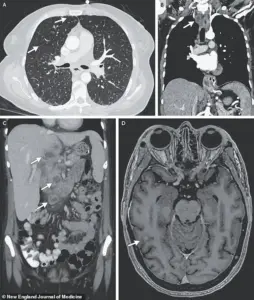

Doctors observed worsening oxygen levels and labored breathing, prompting a series of scans.

X-rays revealed small nodules in her lungs, a telltale sign of bacterial infection.

Further imaging uncovered lesions in her liver, lymph nodes, pancreas, and brain—indications that the infection had spread far beyond her respiratory system.

Consider the case of a woman whose medical scans revealed nodules in multiple organs, including her lungs, liver, pancreas, and brain.

These images, captured through advanced imaging techniques, illustrated the insidious nature of the disease.

TB in the brain can lead to catastrophic outcomes, damaging vital tissues and increasing pressure within the skull.

This pressure can cause nerve cells to die, resulting in paralysis, strokes, or even death.

Such cases highlight the importance of early detection and treatment, as the disease’s ability to infiltrate and damage organs beyond the lungs makes it particularly dangerous if left unchecked.